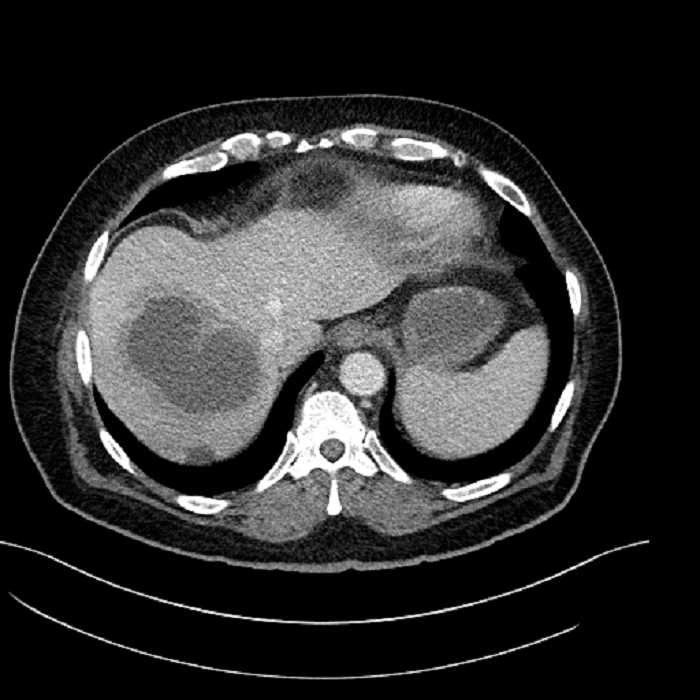

• Large fluid density structure in hepatic segments 7 and 8 measuring 10 x 7 x 7 cm with internal septation and circumferential ill-defined low density compatible with edema

• Hepatic abscess

Acute sigmoid diverticulitis complicated by a small contained perforation and a large abscess in the right hepatic lobe. Additional small subcapsular abscesses along the anterior margin of the left hepatic lobe.

• The classic CT imaging appearance is a double target sign with internal low density surrounded by an internal enhancing rim (capsule) and a low density external rim (edema)

Hepatic abscess showing the double target sign with low density internally surrounded by a thin inner enhancing rim (red arrow) and ill-defined outer low density rim (yellow arrow). Blue arrow indicates an internal septation. Red arrows: additional smaller subcapsular abscesses. Red arrow: focal contained perforation associated with diverticulitis.